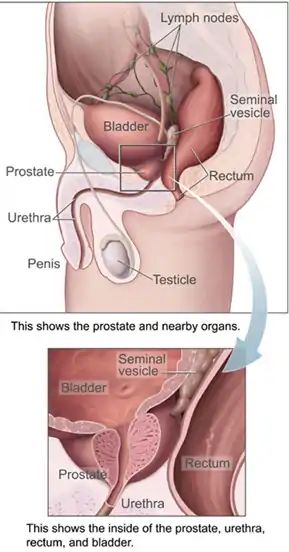

Pathophysiology

The prostate is part of the male reproductive system that helps make and store seminal fluid. In adult men, a typical prostate is about 3 cm long and weighs about 20 g.[57] It is located in the pelvis, under the urinary bladder and in front of the rectum. The prostate surrounds part of the urethra, the tube that carries urine from the bladder during urination and semen during ejaculation.[58] The prostate contains many small glands, which make about 20% of the fluid constituting semen.[59]

Superiorly, the prostate base is contiguous with the bladder outlet. Inferiorly, the prostate's apex heads in the direction of the urogenital diaphragm, which is pointed anterio-inferiorly. The prostate can be divided into four anatomic spaces: peripheral, central, transitional, and anterior fibromuscular stroma.[60] The peripheral space contains the posterior and lateral portions of the prostate, as well as the inferior portions of the prostate. The central space contains the superior portion of the prostate including the most proximal aspects of the urethra and bladder neck. The transitional space is located just anterior to the central space and includes urethra distal to the central gland urethra. The neurovascular bundles course along the posterolateral prostate surface and penetrate the prostatic capsule there as well.

Most of the glandular tissue is found in the peripheral and central zones (peripheral zone: 70-80% of glandular tissue; central zone: 20% of glandular tissue).[61] Some is found in the transitional space (5% of glandular tissue). Thus, most cancers that develop from glandular tissue are found in the peripheral and central spaces,[62] while about 5% is found in the transitional space. None is found in the anterior fibromuscular stroma since no glands are in that anatomic space.

The prostate glands require male hormones, known as androgens, to work properly. Androgens include testosterone, which is made in the testes; dehydroepiandrosterone, made in the adrenal glands; and dihydrotestosterone, which is converted from testosterone within the prostate itself. Androgens are also responsible for secondary sex characteristics such as facial hair and increased muscle mass.

Because of the prostate's location, prostate diseases often affect urination, ejaculation, and rarely defecation. In prostate cancer, the cells of these glands mutate into cancer cells.

Most prostate cancers are classified as adenocarcinomas, or glandular cancers, that begin when semen-secreting gland cells mutate into cancer cells. The region of the prostate gland where the adenocarcinoma is most common is the peripheral zone. Initially, small clumps of cancer cells remain within otherwise normal prostate glands, a condition known as carcinoma in situ or prostatic intraepithelial neoplasia (PIN). Although no proof establishes that PIN is a cancer precursor, it is closely associated with cancer. Over time, these cells multiply and spread to the surrounding prostate tissue (the stroma) forming a tumor.

Eventually, the tumor may grow large enough to invade nearby organs such as the seminal vesicles or the rectum, or tumor cells may develop the ability to travel in the bloodstream and lymphatic system.

Prostate cancer is considered a malignant tumor because it can invade other areas of the body. This invasion is called metastasis. Prostate cancer most commonly metastasizes to the bones and lymph nodes, and may invade the rectum, bladder, and lower ureters after local progression. The route of metastasis to bone is thought to be venous, as the prostatic venous plexus draining the prostate connects with the vertebral veins.[63]